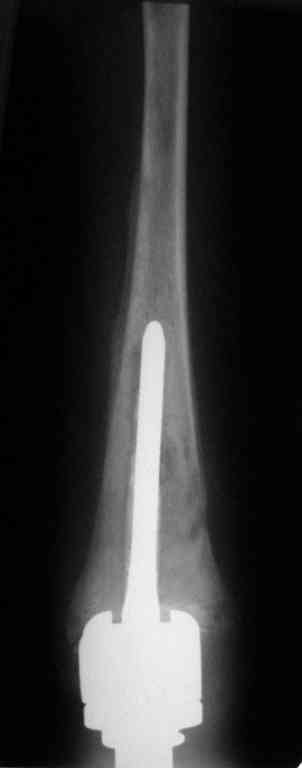

Уважаемые коллеги! Хотелось бы узнать ваше мнение о тактике лечения пациентки 16 лет, диагноз - б-нь Гоше I типа, состояние после резекции проксимальных 2/3 левой большеберцовой кости, тотального эндопротезирования ЛКС онкологическим эндопротезом, перипротезная инфекция.

Протез установлен год назад, в течение 8 месяцевфункционируют свищи, сообщающиеся с компонентами эндопротеза.

Пациентку беспокоят боли в нижней трети голени при физической нагрузки.